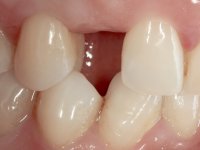

The patient wanted to "replace a milk tooth that fell” and would like a fixed tooth, but did not want to extract the impacted tooth, nor to place an implant.

Female patient, 43 years old, non-smoker. Showed an edentulous space in the upper right canine area, resulting from tooth 1.3 impaction. The space had a mesio-distal diameter reduced to the normal size of the upper canine. This is consistent with the presence in the arch of the deciduous canine up to two years ago). Orthopantomography allows clearly view of tooth 1.3 impaction.The patient has a thick gingival phenotype and tolerable oral hygiene.